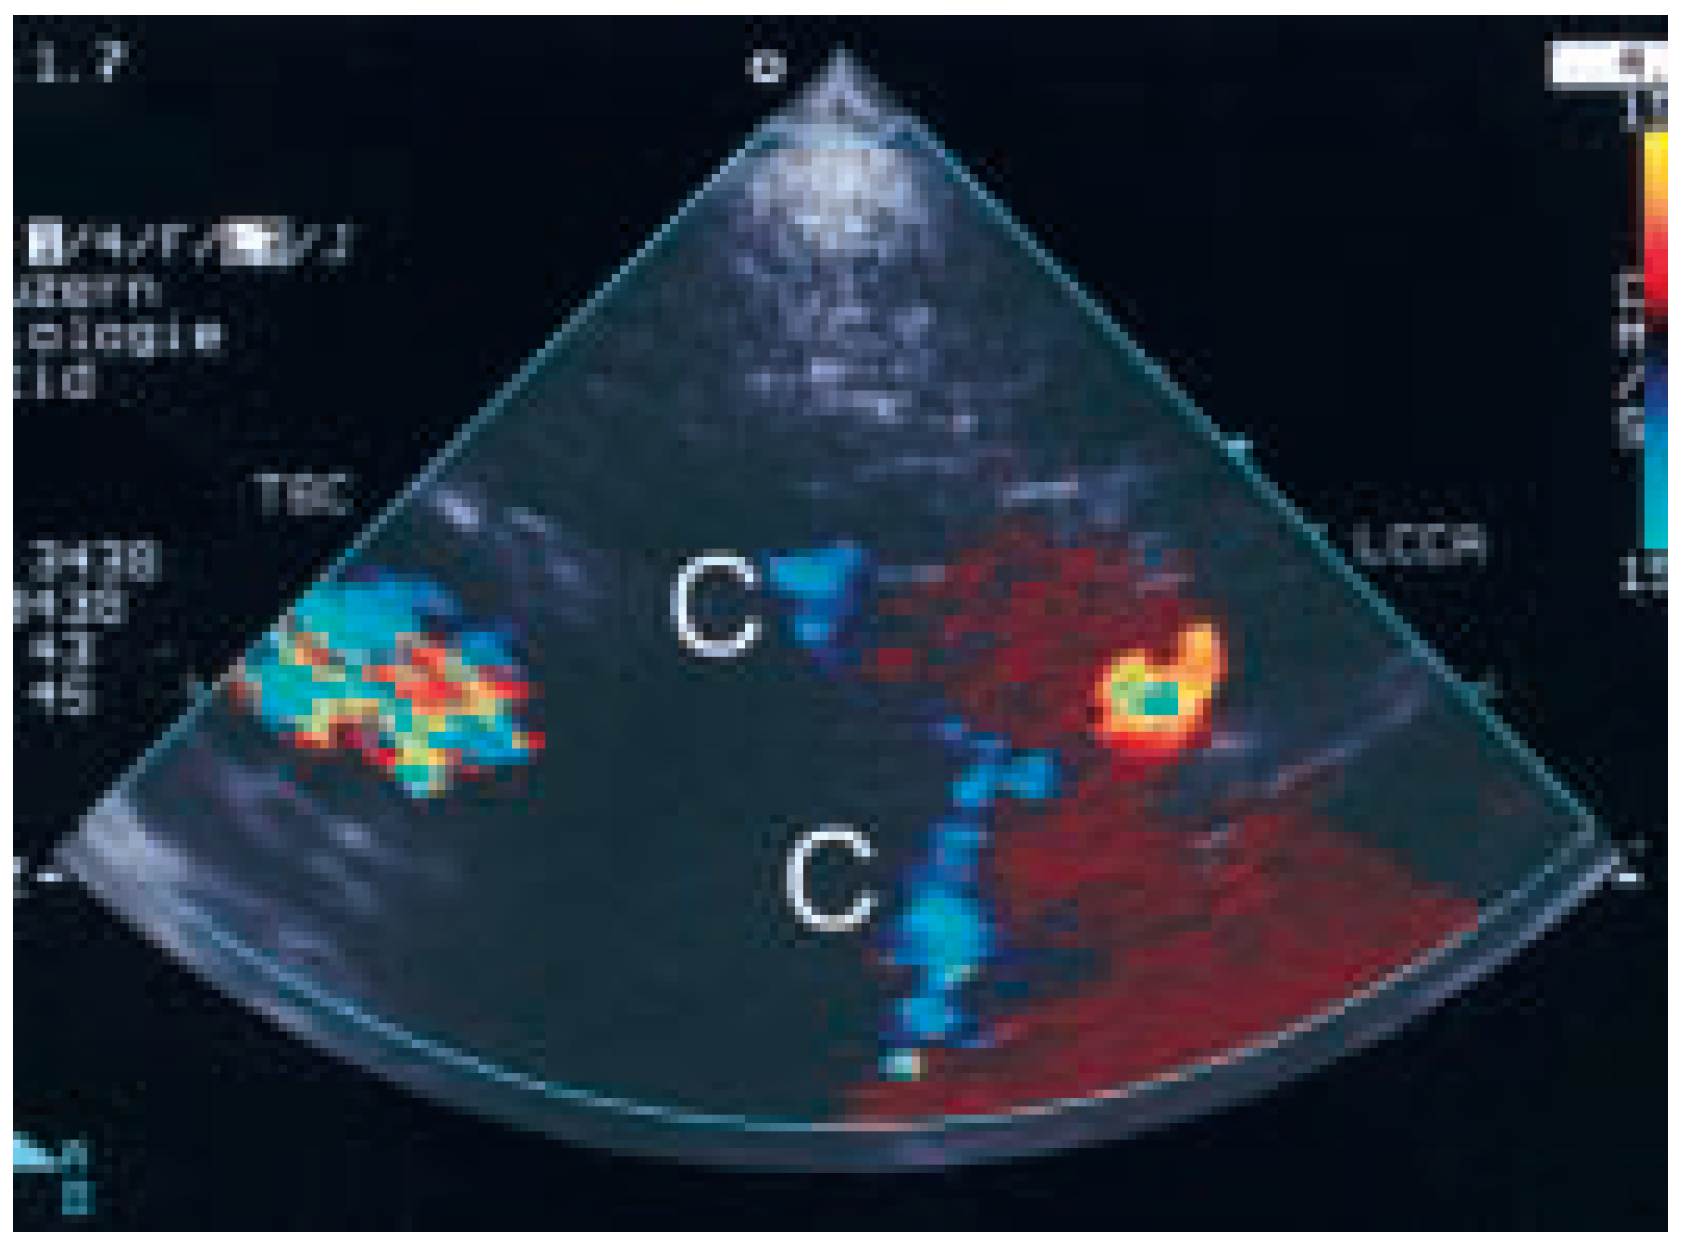

A fourtynine-year-old man without clinical symptoms nor relevant illnesses prior to the hospitalisation was admitted due to a large anteroseptal and apical infarct and presented with biventricular dysfunction. During followup ejection fraction of the patient with one vessel disease rose from 31 to 45% within four weeks following percutaneous revascularisation of an occluded middle left anterior descending artery (LAD) by use of a stent. Despite high doses of various diuretics such as furosemide and aldactone, in addition to angiotensin converting enzyme inhibitor, digoxin and betablockade, follow-up was characterised by persistent elevated jugular venous pressure (Figure 1) with pleural effusion mainly on the right side (Figure 2), indicating right ventricular dysfunction or hypotensive state. Suprasternal colour Doppler sonography revealed thrombosed proximal superior vena cava with collaterals (Figure 3). Computer tomography showed an enlarged azygos vein with thrombosed proximal superior vena cava and multiple collaterals (Figure 4) and retrosternal calcification (Figure 5). However, distal vena cava was open (Figure 6). Lymph node and adjacent tissue inflammation most probably due to tuberculosis in early childhood caused the thrombosis in the proximal part of the superior vena cava.

Figure 3. Suprasternal colour Doppler sonography revealed thrombosed proximal superior vena cava with collaterals. C = collaterals; LCCA = left common carotid artery; TBC = brachiocephalic artery.